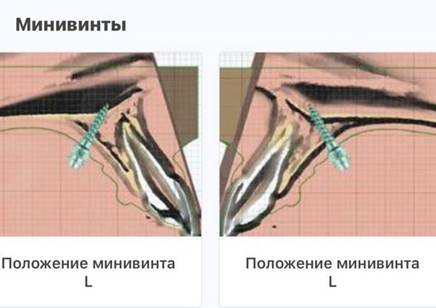

Цель аппарата — не просто давить куда попало, а приложить строго выверенное усилие для раскрытия нёбного шва. Винты, если они нужны, — тоже не простые: мы используем бикортикальные. У кости есть два плотных кортикальных слоя — твёрдых, как яичная скорлупа. Один — со стороны рта, другой — со стороны полости носа. Винт должен пройти через оба этих слоя. Это даёт очень плотную и жёсткую фиксацию, которая позволяет создать то самое сверхусилие, чтобы раздвинуть кости.

Для точной установки печатаем 3D-шаблоны — назубные капы с отверстиями, через которые хирург вводит инструмент.

Риск ошибки тут очень велик: если хоть чуть-чуть ошибёшься во время установки винта, то потом заглушка аппарата просто не сядет вовнутрь, и придётся всё переделывать.

Так как молочных зубов у Даши уже не было, а нёбный шов был более зрелым, мы выбрали аппарат на мини-винтах, который называется MARPE (Miniscrew-Assisted Rapid Palatal Expansion). После его установки и активации, когда родители специальным ключиком раскручивали винт, у неё между передними зубами появилась заметная щель. Родители иногда пугаются, но для нас это лучший признак того, что расширение идёт как надо.

Аппарат MARPE: его ставят детям постарше — примерно с 11 лет. В этом возрасте нёбный шов уже плотный, поэтому нужна дополнительная опора на кость. Для этого используются мини-винты. Главное — установить их так, чтобы давление распределялось равномерно, а половинки нёба расходились параллельно. Если ошибиться с положением, то можно получить асимметрию или наклон костных сегментов. Как говорится, одна ошибка — и ты ошибся. Место установки выбираем по КТ: ищем кости поплотнее, ведь в мягкой винт может расшататься. При этом важно найти сегмент, где не только кость плотная, но ещё и нагрузка в нужную сторону направлена, и в целом винты со всей остальной анатомией взаимно вежливы.